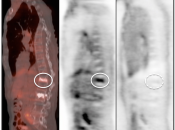

Value of Non-Attenuation Corrected (NAC) Images

Resolving Attenuation Correction Artifacts:

The CT images obtained during an exam are not only used for “anatomic” interpretation. They are also used for “attenuation correction” (AC) of the PET images, generating the much more useful AC PET images used for interpretation.

Unfortunately, attenuation correction of PET images can result in falsely elevated metabolic activity in regions of high CT density (e.g. metallic devices, oral contrast, calcification).

In such cases, these areas must be reviewed on the NAC (non-attenuation correction) images. If these regions are not also hypermetabolic on the NAC images, then their apparent increased FDG-uptake on the AC images is artefactual.

This phenomenon is almost exclusively seen with older PET/CT scanners, as most modern scanners utilize newer algorithms that do not “over-correct” in these areas of increased density.